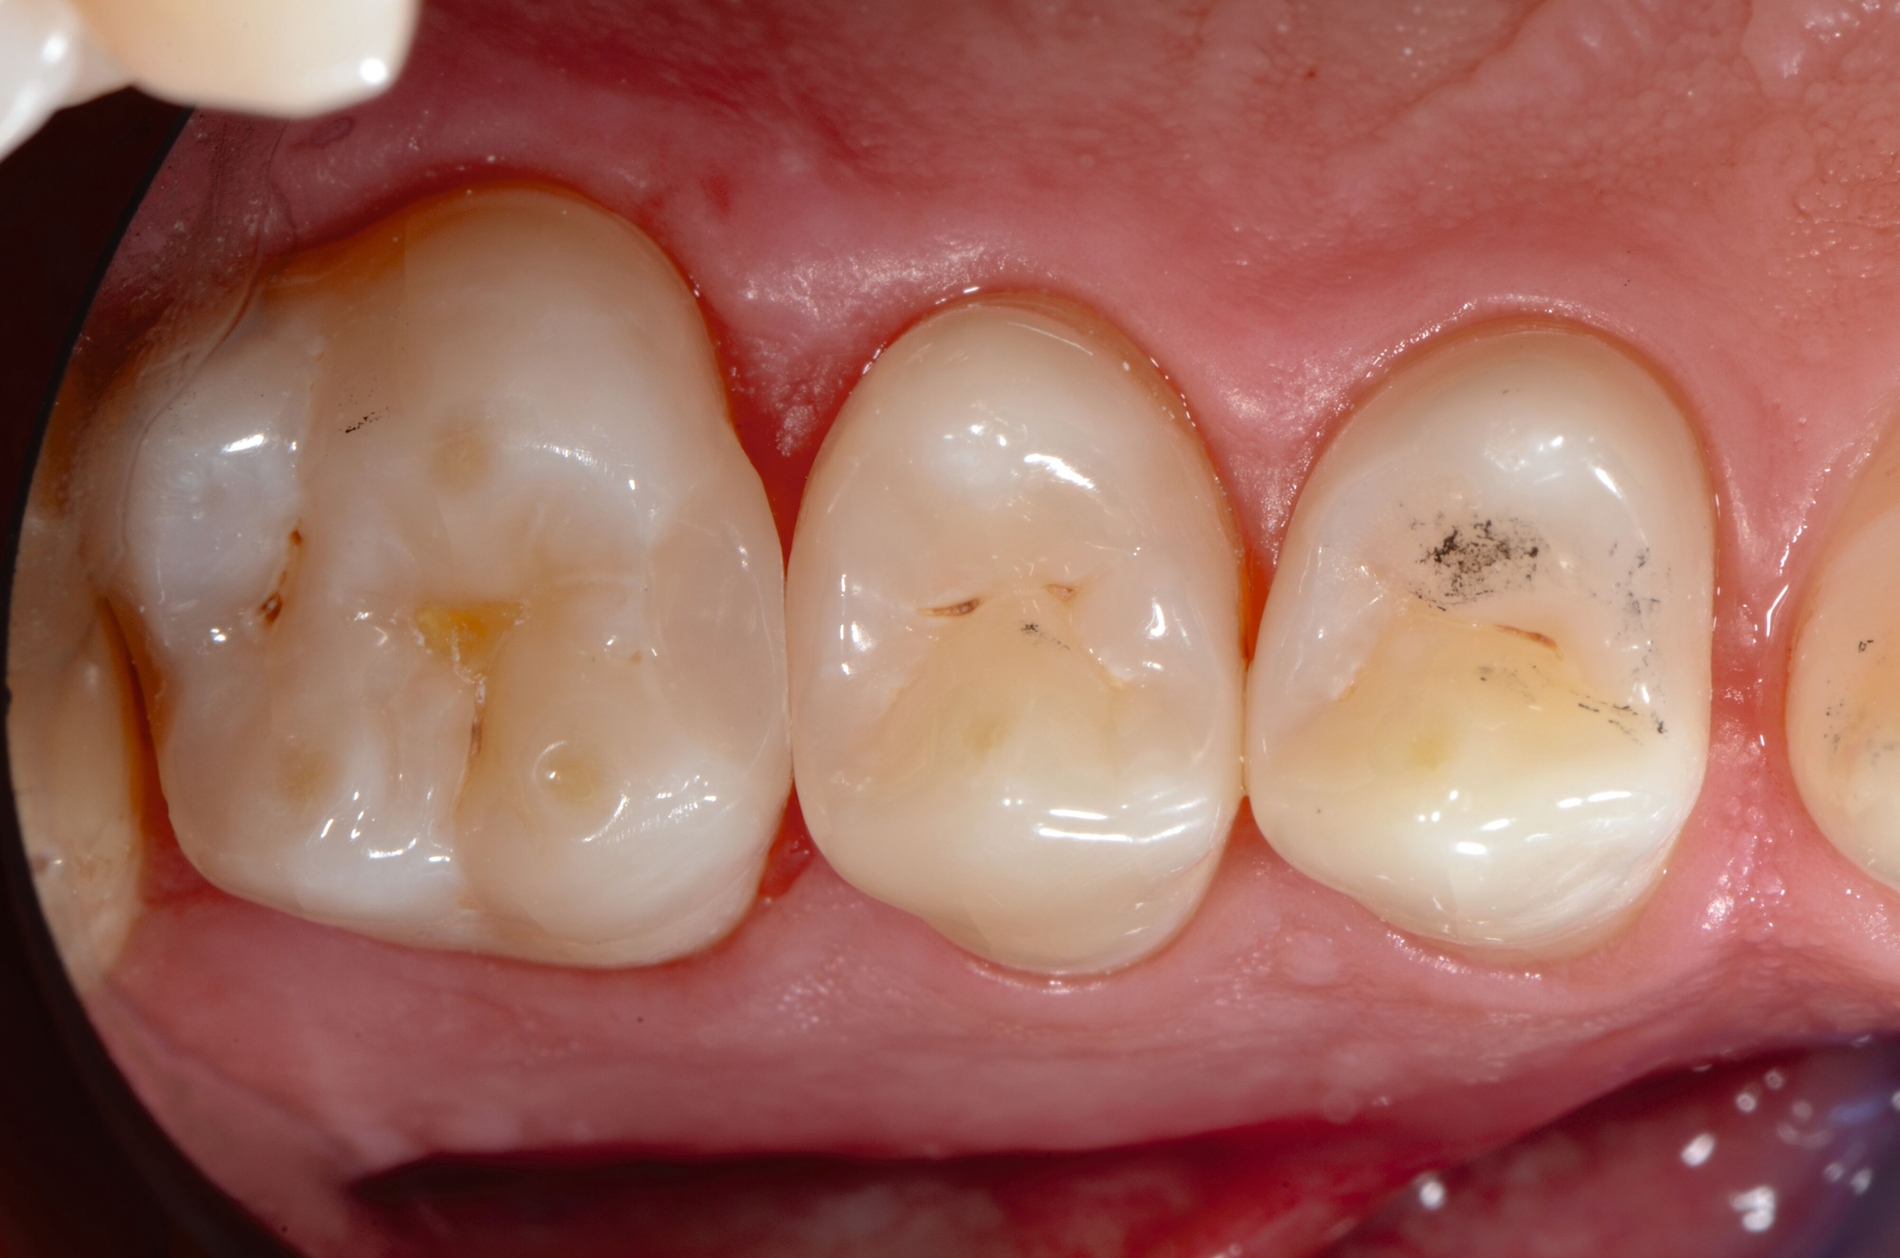

Adhäsivsysteme gewährleisten bei Einhaltung des Adhäsivprotokolls einen sehr festen Verbund zwischen Kompositen und Zahnhartsubstanzen. Bei Betrachtung der Studienlage zu den verschiedenen Generationen und Entwicklungsstufen der Adhäsivsysteme zeigte sich in älteren Studien, dass 2-Schritt-Self-Etch- und 3-Schritt-Etch-and-Rinse-Adhäsivsysteme signifikante Vorteile in Bezug auf Haltbarkeit und Widerstandsfähigkeit gegen Sekundärkaries bieten. Moderne Universaladhäsive erzielen ähnliche Ergebnisse (Abbildung 2). Diese Adhäsivsysteme sollten insofern bei der direkten Komposittechnik angewendet werden. Phosphorsäureätzung wird in diesem Zusammenhang nach wie vor für die Ätzung des Schmelzes empfohlen, da deutliche Vorteile bei der Schmelzhaftung und damit auch zur Reduzierung von marginalen Randqualitäten berichtet werden [Peumans et al., 2005; Schwendicke et al., 2016; Askar et al., 2021; de Assis et al., 2020; Krithikadatta, 2010; Mahn et al., 2015; Szesz et al., 2016].